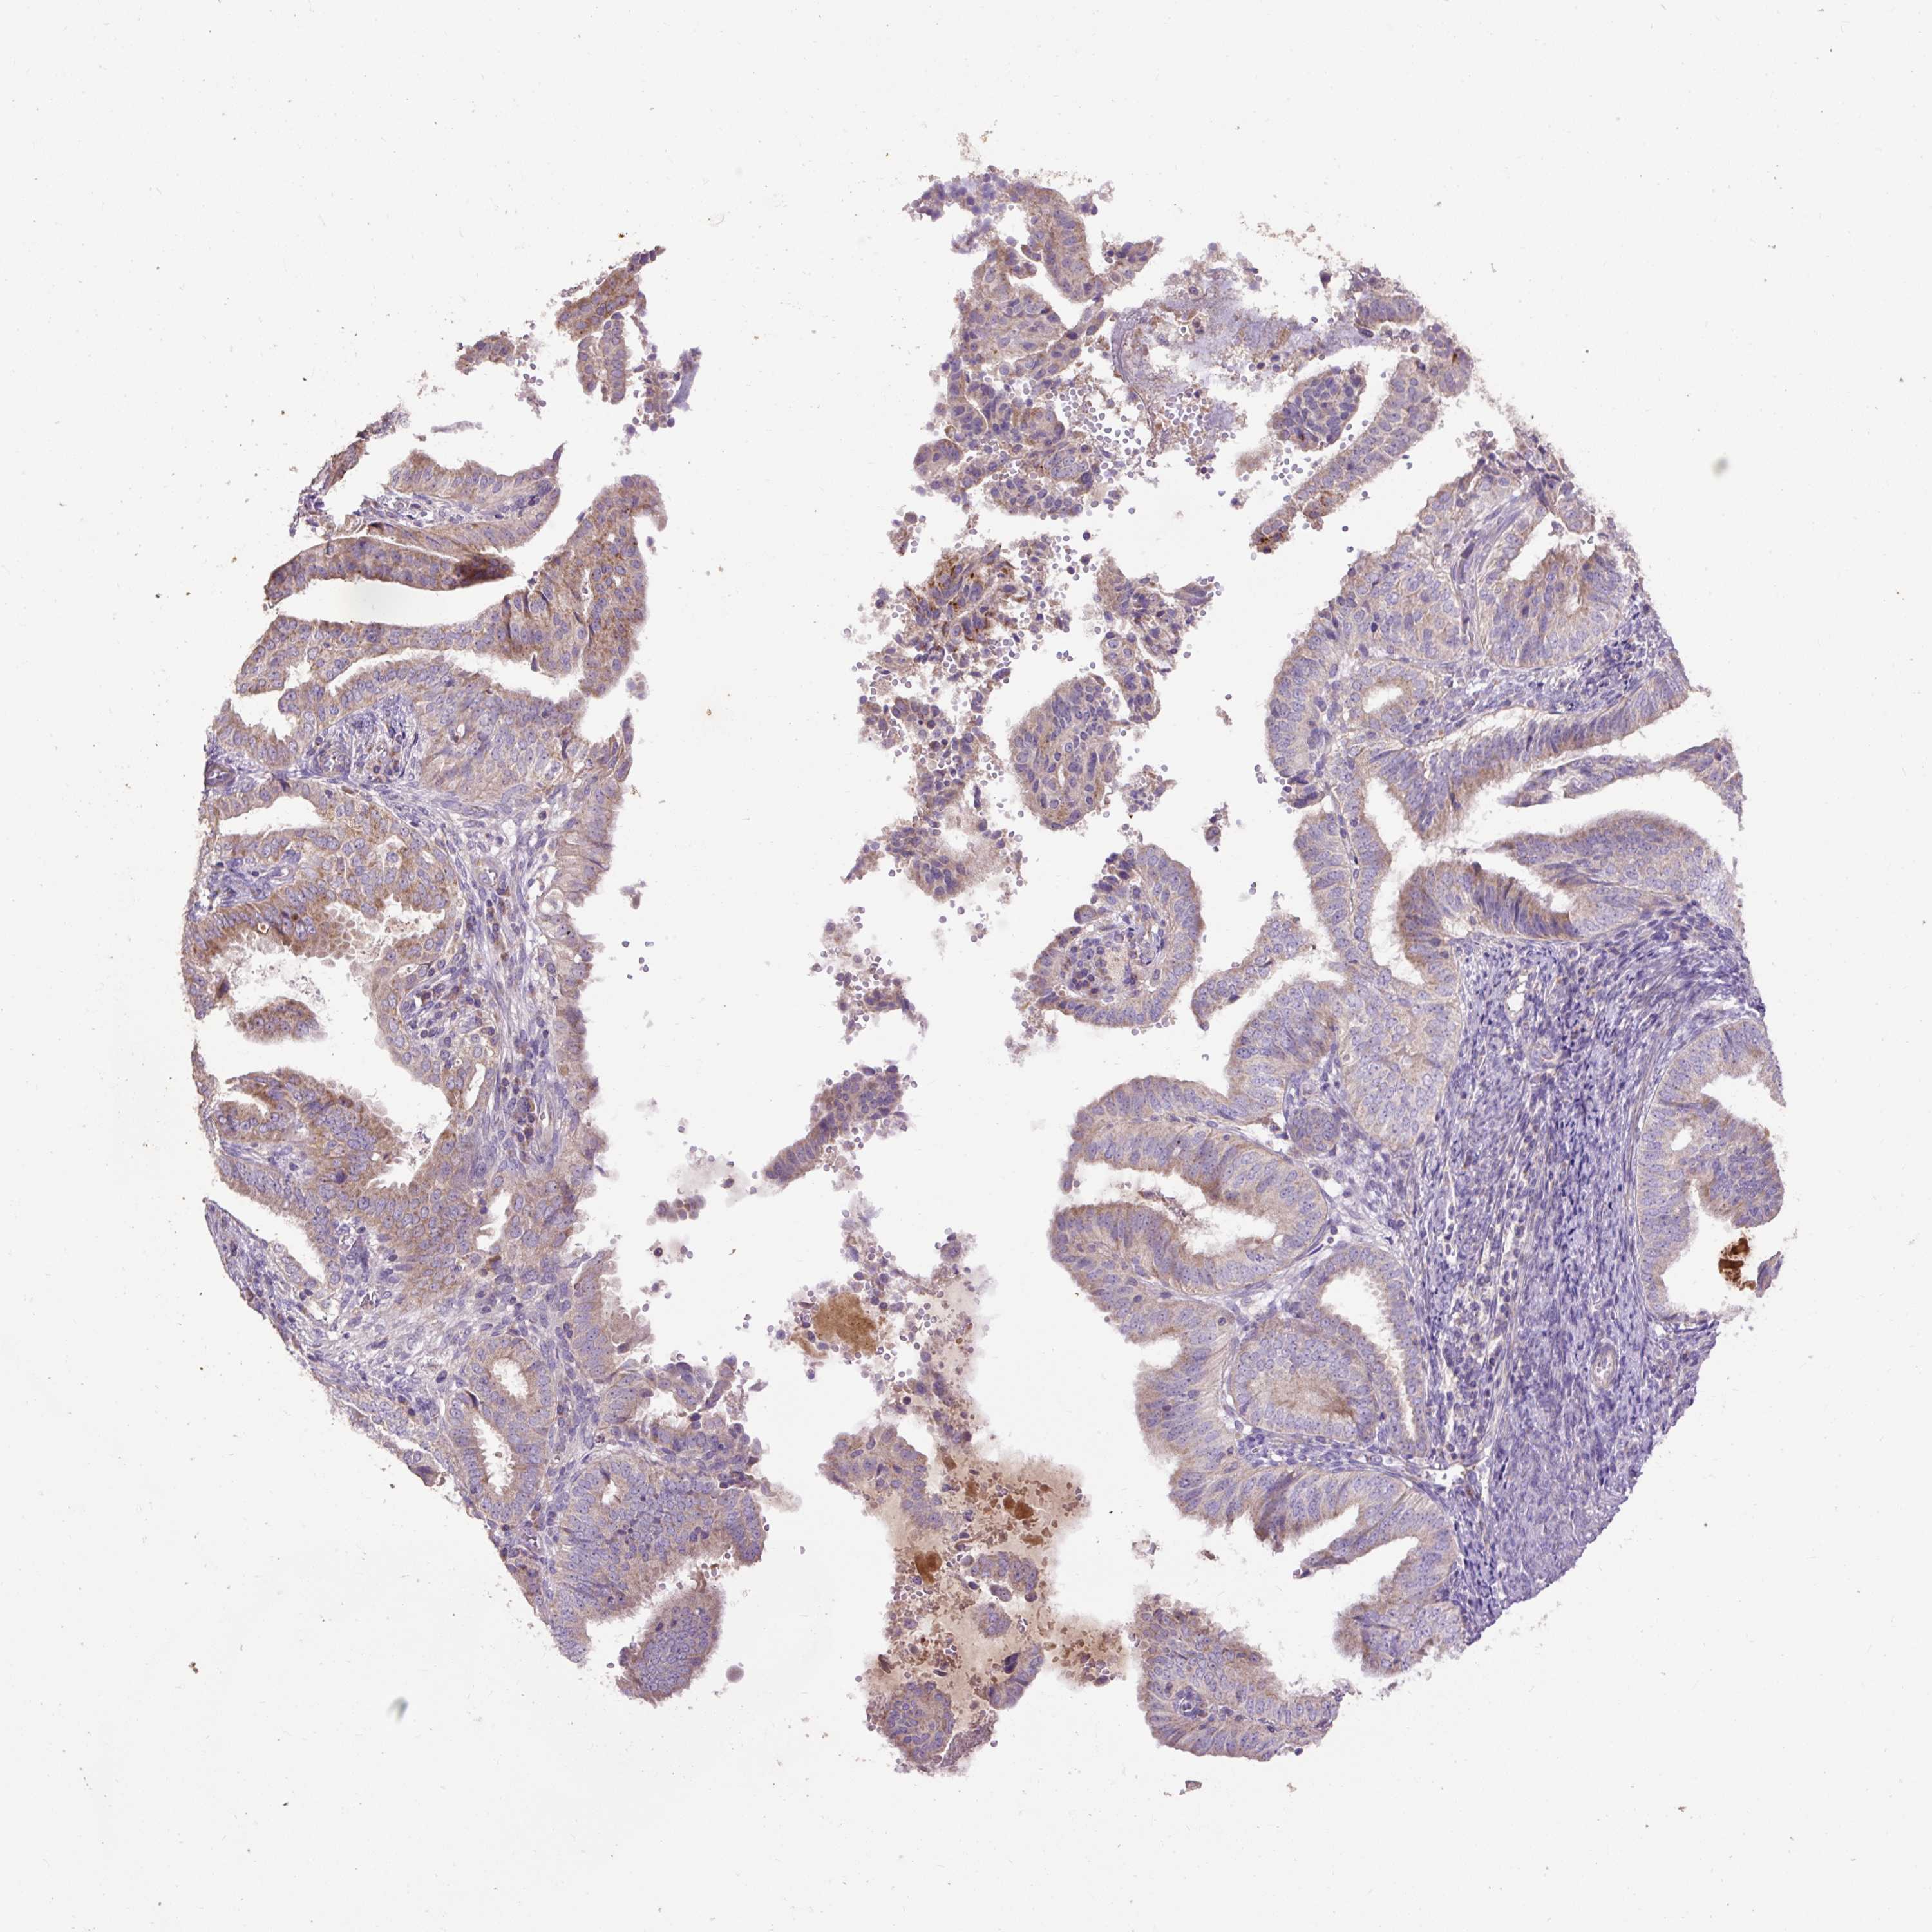

ENDOMETRIAL CANCER - Protein expressioni

A mouse-over function shows sample information and annotation data. Click on an image to view it in a full screen mode. Samples can be filtered based on level of antibody staining by selecting one or several of the following categories: high, medium, low and not detected. The assay and annotation is described here.

Note that samples used for immunohistochemistry by the Human Protein Atlas do not correspond to samples in the TCGA dataset.

Antibody stainingi

Antibody staining in the annotated cell types in the current human tissue is reported as not detected, low, medium, or high, based on conventional immunohistochemistry profiling in selected tissues. This score is based on the combination of the staining intensity and fraction of stained cells.

Each image is clickable and will lead to virtual microscopy that enables deeper exploration of all samples and also displays staining intensity scores, fraction scores and subcellular localization as well as patient and tissue information for each sample.

Antibody HPA054824

Staining

High

Medium

Low

Not detected

Intensity

Strong

Moderate

Weak

Negative

Quantity

>75%

75%-25%

<25%

None

Location

Nuclear

Cytoplasmic/membranous

Cytoplasmic/membranous,nuclear

Adenocarcinoma, NOS